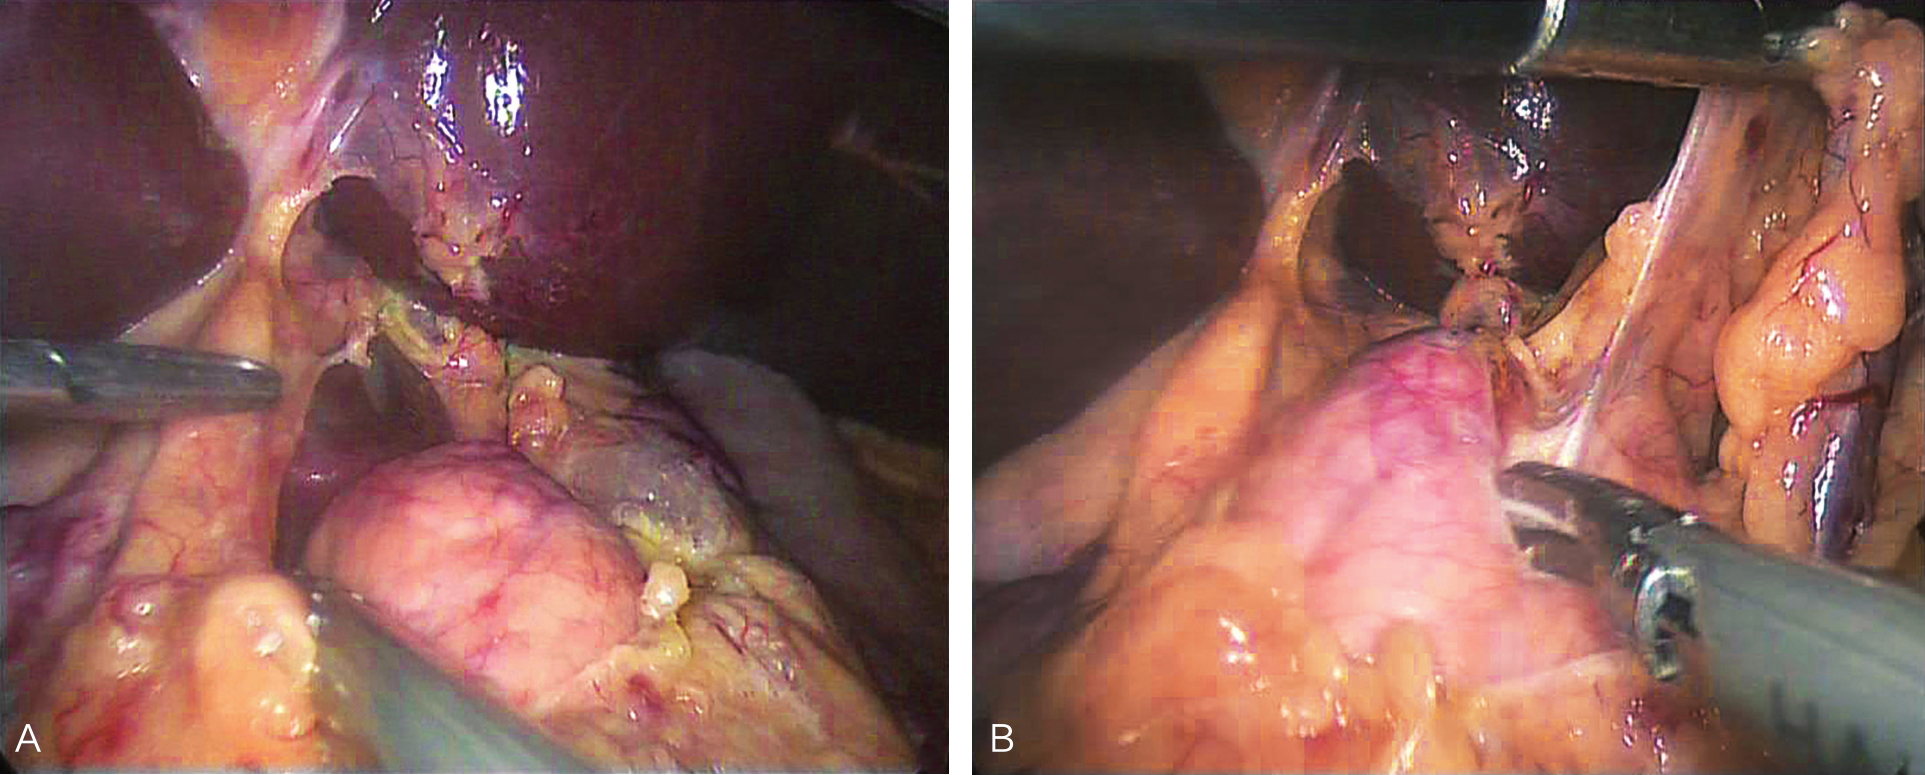

患者取平卧位,头高脚低,四孔或三孔法操作;首先自胃网膜血管弓下方横行打开胃结肠韧带(图6-1),探查胰腺颈、体、尾,必要时可打开胰腺下缘被膜,游离胰腺后方深入探查;清楚定位肿瘤后,镜下缝合肿瘤一针作为牵引用(图6-2),超声刀紧贴肿瘤,完整剜除;检查胰腺创面,选择性缝合创面(图6-3);取出标本,送冰冻,留置引流,关闭腹壁切口,术毕(图6-4)。

图6-1 经胃结肠韧带无血管区,超声刀离断

图6-2 定位肿瘤后,缝合肿瘤后牵引肿瘤